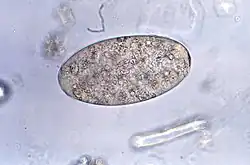

![]() Huevo de Fasciolopsis buski | ||

Los adultos producen más de 25.000 huevos al día, que tardan hasta siete semanas en madurar y eclosionar a 27-32 °C. Los huevos no embrionados, inmaduros, se descargan en el intestino y las heces. En dos semanas, los huevos se embrionan en agua, y después de aproximadamente siete semanas, los huevos liberan pequeños organismos parásitos llamados miracidios, que invaden un caracol, el huésped intermediario adecuado. Varias especies de los géneros Segmentina y Hippeutis sirven como huéspedes intermediarios. En el caracol, el parásito sufre varias etapas de desarrollo (esporoquistes, rediae y cercarias). Las cercarias se liberan del caracol y se enquistan como metacercarias en plantas acuáticas tales como castaño de agua, callo de agua, loto, bambú y otras plantas comestibles. El huésped final de los mamíferos se infecta al ingerir metacercarias en las plantas acuáticas. Después de la ingestión, las metacercarias excretan en el duodeno en aproximadamente tres meses y se unen a la pared intestinal. Allí se desarrollan en trematodos adultos (20 a 75 mm por 8 a 20 mm) en aproximadamente 3 meses, unidos a la pared intestinal de los huéspedes mamíferos (humanos y cerdos). Los adultos tienen una vida de aproximadamente un año.